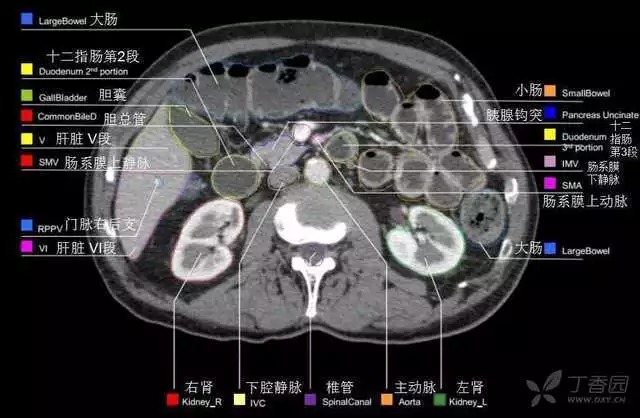

腹部肝脏高清CT断层的图谱

全腹部高清CT图谱,淋巴结彩色图谱,血管解剖图谱大汇总!

超声肝脏分叶及分段

肝脏分段和基本解剖学标志